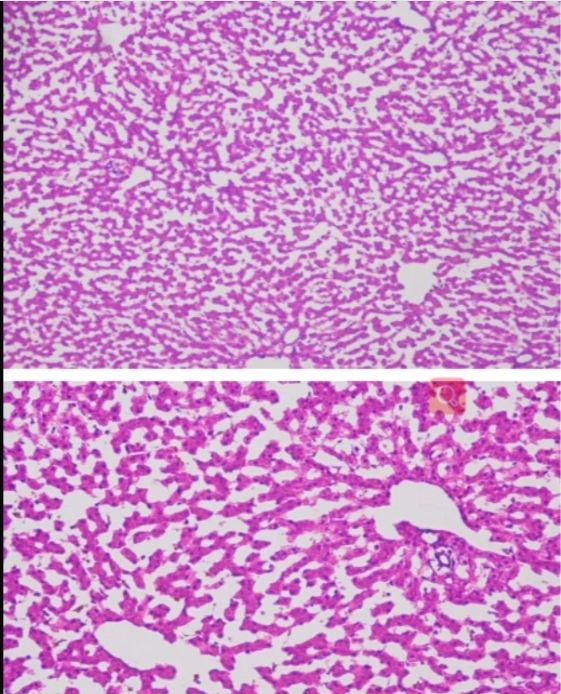

小鼠大腦冰凍切片